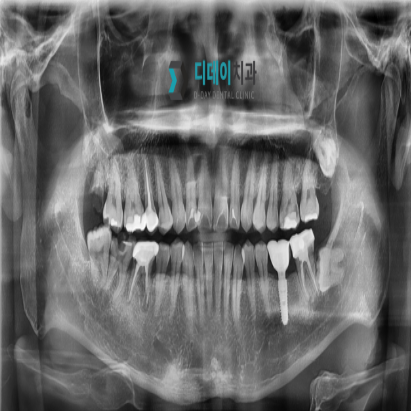

<전> 230622

<후> 240212

게시물의 치료 사진은 실제 본원에서 모든 치료 과정을 마친 환자분의 동의하에 촬영되었습니다. 전후 사진은 동일인이며, 동일 조건하에 촬영되었음을 밝힙니다.